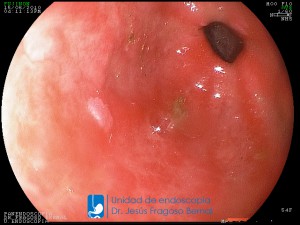

La Unidad de Endoscopía fue creada en 2002 por el Dr. Jesús Fragoso Bernal, es pionera en el estado por la utilización de la tecnología más avanzada, que nos permite ofrecer servicios integrales de diagnóstico y tratamiento para las enfermedades del aparato digestivo.